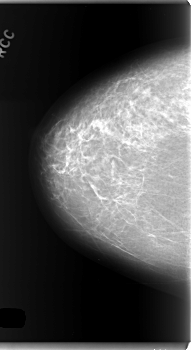

C_0106_1.RIGHT_CC

RIGHT_CC LINES 5944 PIXELS_PER_LINE 3240 BITS_PER_PIXEL 12 RESOLUTION 50 NON_OVERLAY